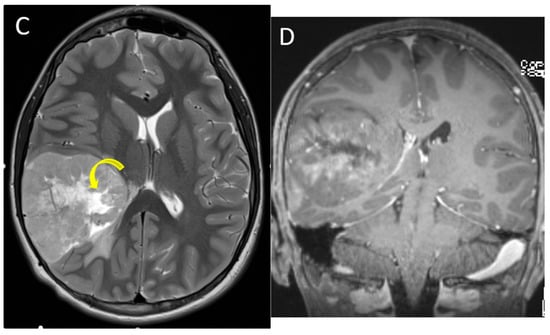

| Diffuse midline glioma (H3K27 altered) | Ventral pons and thalami | Expansile, ill-defined mass No diffusion restriction Usually, non-enhancing at presentation Encasement of basilar artery without narrowing |

| Supratentorial high-grade glioma (H3 G34 mutant or H3 wild-type) | Hemispheric or deep nuclei; most common in frontal and parietal lobes | Large, circumscribed tumor Diffusion restricting solid components Variable cysts/necrosis and hemorrhage |